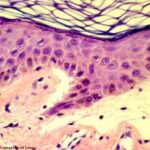

Histopathology. The bullous pemphigoid-like presentation described above is the most common form of EBA. The subepidermal blisters are inflammatory. The predominant infiltrating cells are lymphocytes and neutrophils in perivascular and focal interstitial array. Eosinophils are present in variable numbers . In the classic form, the subepidermal blisters are noninflammatory ; fibrosis and milia formation are often present. |

IF Testing. Examination of perilesional skin using DIF reveals linear deposition of complement at the basement membrane zone in the vast majority of cases. IgG is by far the most common immunoglobulin found, but IgM and IgA may be present as well. Increasing numbers of immunoglobulin subclasses noted at the dermal-epidermal junction favor a diagnosis of EBA over bullous pemphigoid. The presence of linear C3 at the dermal-epidermal junction alone favors bullous pemphigoid over EBA. However, use of routine DIF cannot reliably distinguish between bullous pemphigoid and EBA. IIF reveals circulating anti-basement membrane zone antibodies in up to 50%. |